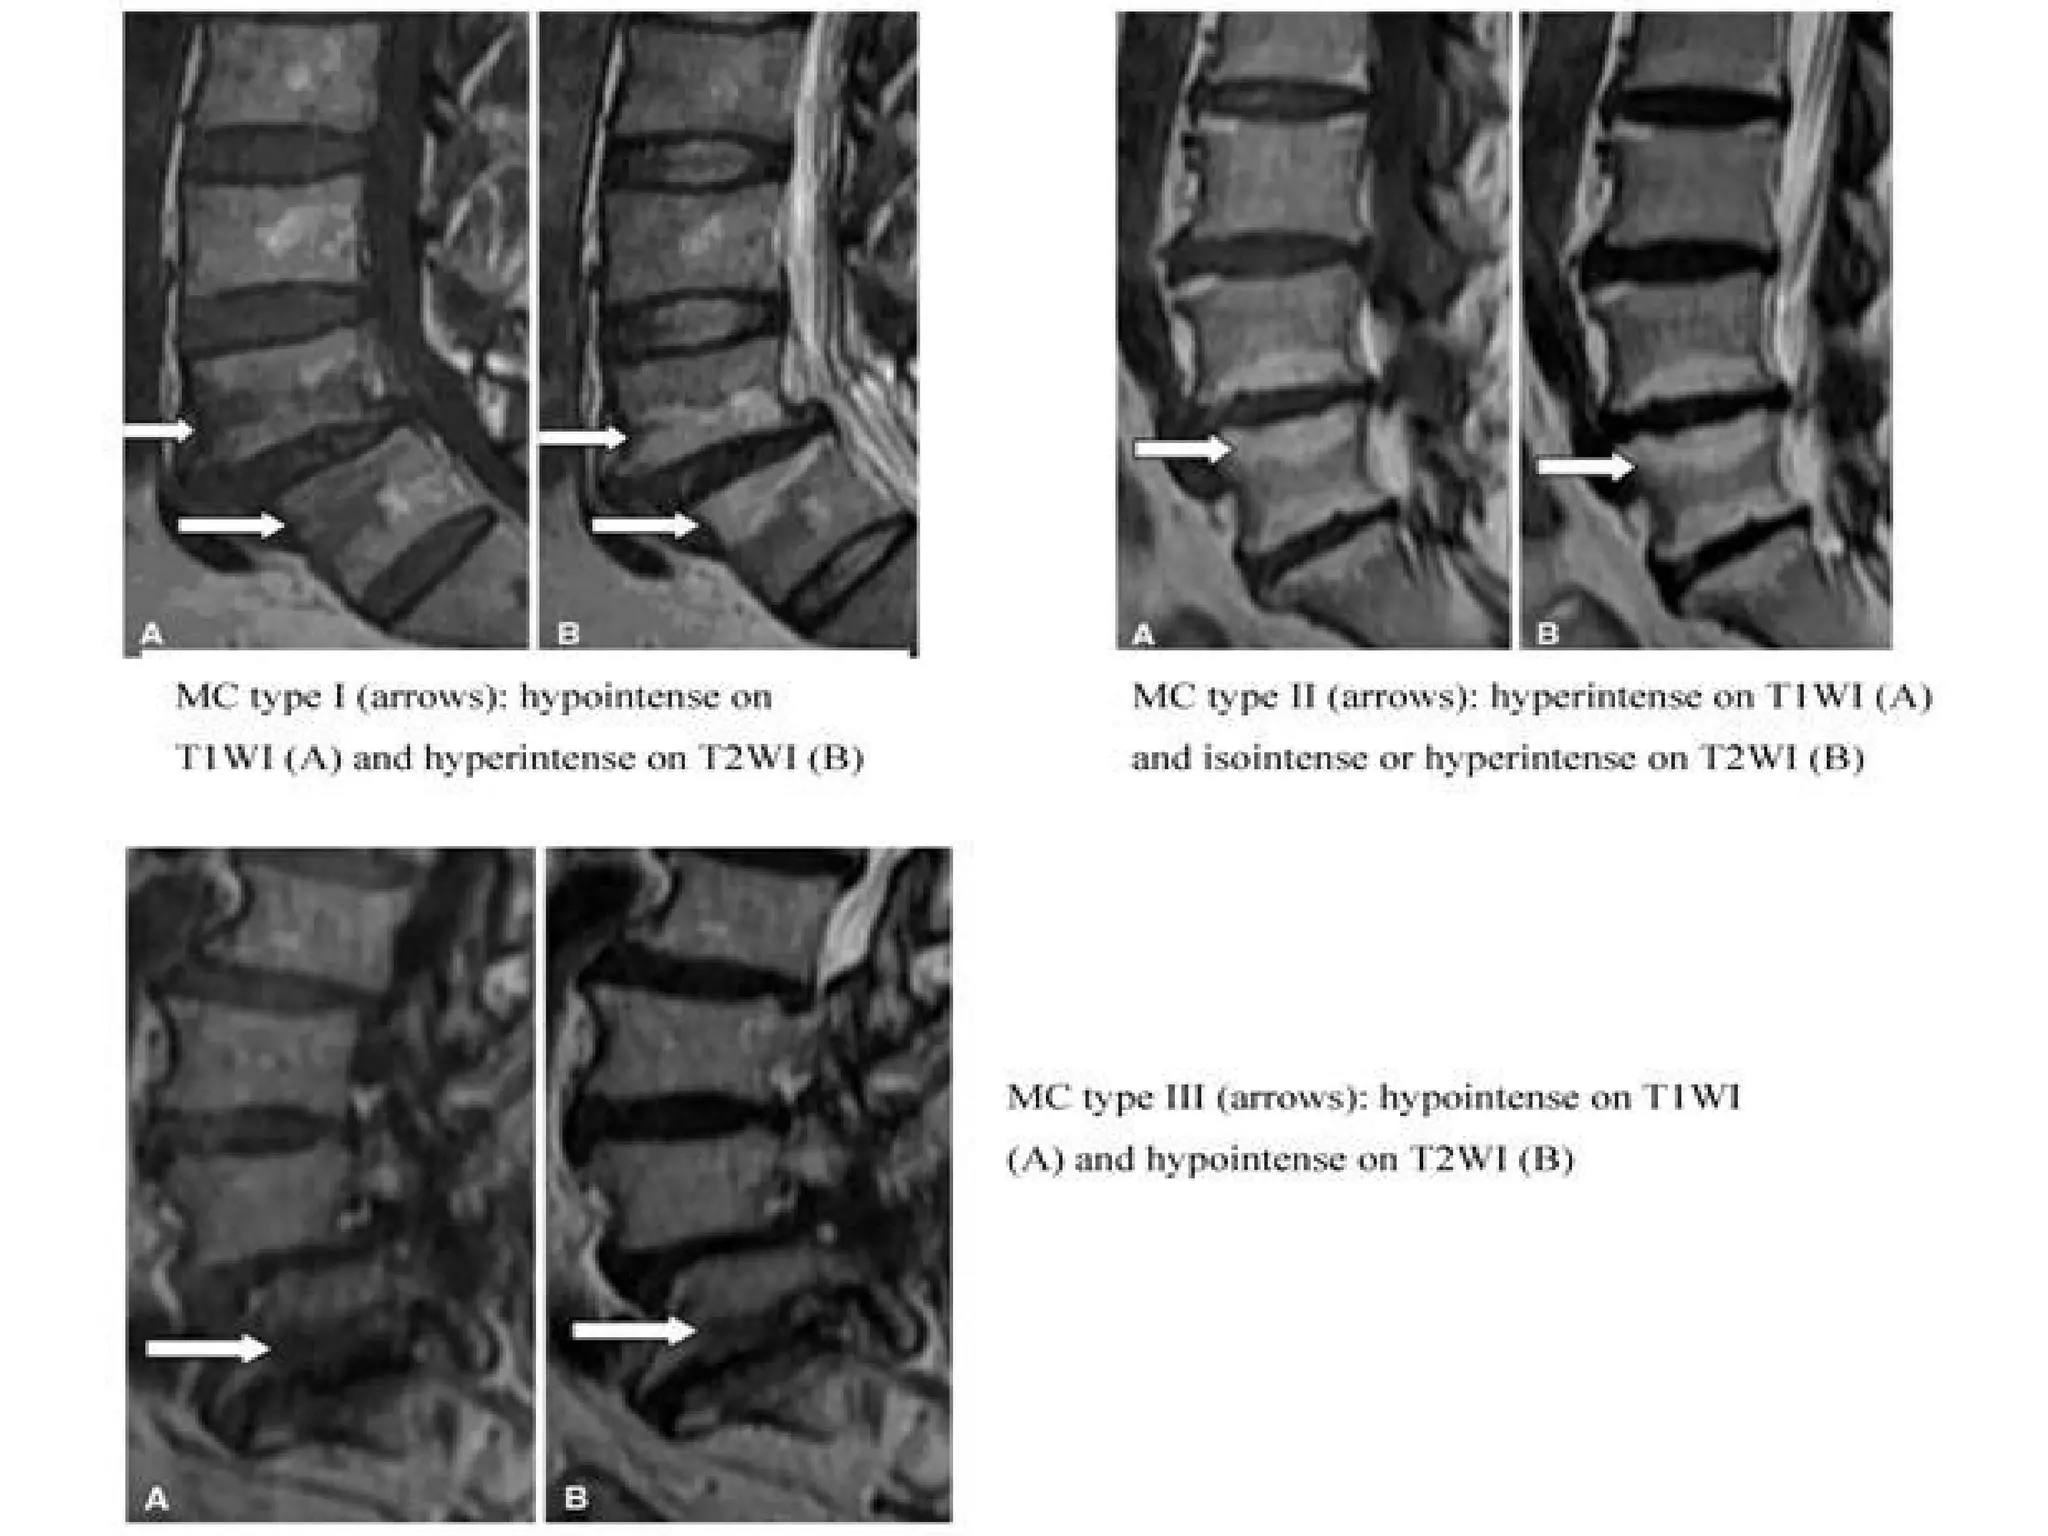

Modic type 1 deg. changes (MI)

Hypointense on T1WI (A)

Hyperintense on T2WI (B)

Modic type 2 degenerative

changes (MII)

hyperintense on T1WI (A)

isointense or slightly hyperintense on T2WI (B)

Modic type 3 degenerative changes

(MIII)

Hypointense on both

T1WI (A) and T2WI (B)